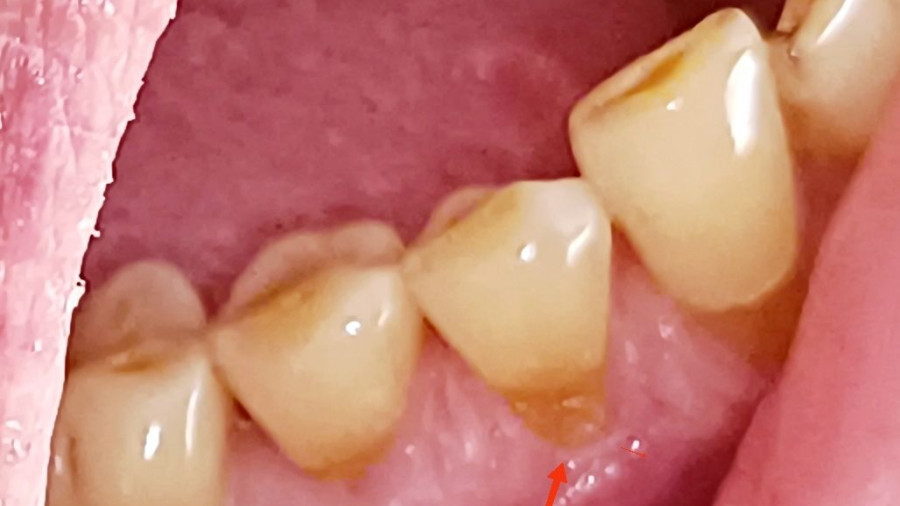

Το δυνατό τρίψιμο μπορεί να φθείρει την αδαμαντίνη των δοντιών (δηλαδή την εξωτερική, προστατευτική τους στοιβάδα) και να προκαλέσει υφίζηση των ούλων, δηλαδή να υποχωρήσουν τα ούλα και να εκτεθούν οι ρίζες των δοντιών. Αυτό οδηγεί σε ευαισθησία και αυξημένο κίνδυνο τερηδόνας.

Τερηδόνα